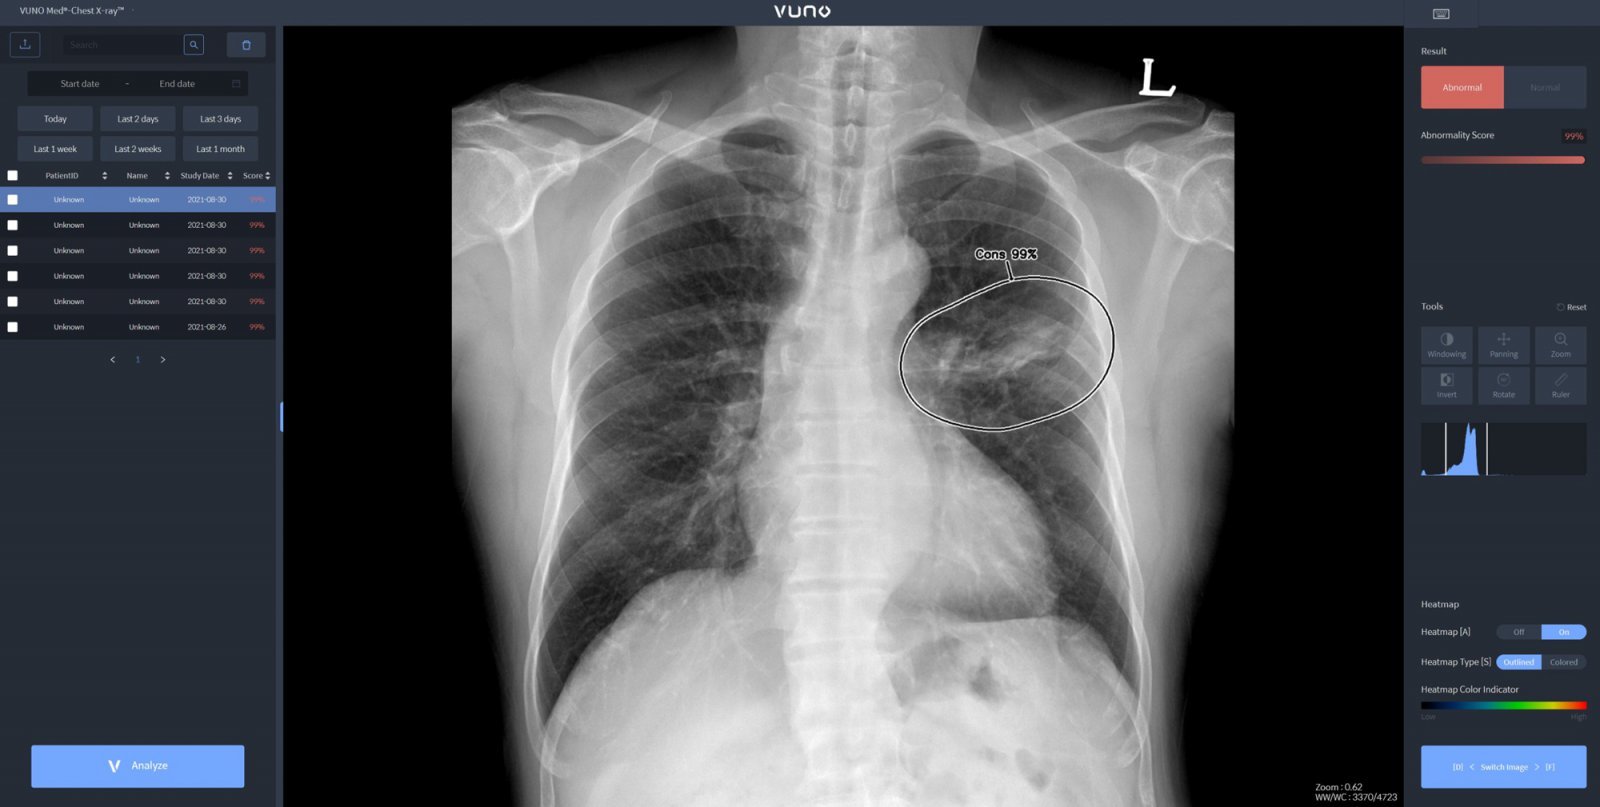

26일 의료계에 따르면 기흉은 폐에 생긴 구멍으로 공기가 새면서 폐 밖(흉막강) 안에 공기가 차는 질환이다.

기흉은 자발성 기흉과 외상성 기흉으로 구분된다. 자발성은 일차성 기흉과 이차성 기흉으로 나뉜다. 일차성 기흉은 건강한 사람에게 발생하며, 폐의 가장 윗부분 흉막에 있는 작은 공기주머니에 의해 발생한다. 일차성 기흉의 원인은 분명하지 않지만 환자의 대부분이 키가 크고 말랐거나 흡연자라는 보고도 있다. 이차성 기흉은 폐질환을 앓고 있던 사람에게 발생한다. 여기에는 결핵, 악성 종양, 폐섬유증, 만성 폐쇄성 폐질환, 폐기종 등이 있다.